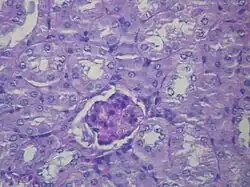

Histological image of a normal kidney glomerulus. It is possible to see a glomerulus in the centre of the image surrounded by kidney tubules.

Nephrotic syndrome has many causes and may either be the result of a glomerular disease that can be either limited to the kidney, called primary nephrotic syndrome (primary glomerulonephrosis), or a condition that affects the kidney and other parts of the body, called secondary nephrotic syndrome.[20]